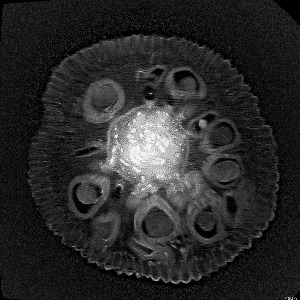

Quizás no sea lo más ortodoxo, pero no podemos negar su componente curioso y llamativo. Seguramente pocos nos imaginaríamos que una fruta de la pasión o la raíz de un apio tienen en su interior un aspecto muy similar al del cerebro. O que las fresas se parecen a un panal de miel. Aclaremos el misterio: esto ocurre cuando las frutas son observadas a través de una resonancia magnética.

Andy Ellison, técnico en resonancias magnéticas del Centro de Imágenes Biomédicas de la Escuela de Medicina de la Universidad de Boston, se ha propuesto enseñarnos de este modo cómo son las entrañas de las verduras y las frutas que comemos a diario. Para ello, ha utilizado la tecnología médica avanzada con la que trabaja para capturar las secciones transversales de estos alimentos, de la misma manera que cada día se hace con el cerebro humano, las rodillas o la columna.

El resultado, que recoge en su blog Inside Insides, son unas fascinantes imágenes y GIFs que nos muestran las frutas y las verduras desde otro punto de vista. Desde un interior tan llamativo y adictivo como lo pueden ser sus colores, formas y sus texturas. La colección es amplia y da para todo tipo de evocaciones, porque por el escáner de Ellison –en concreto, una Philips 3 Tesla MRI, explica– han pasado todo tipo de alimentos, desde los más comunes como las cebollas, los pimientos, los tomates o los plátanos, hasta lichis, la jaca (también conocida como jackfruit, uno de los frutos más grandes del mundo), la fruta del dragón o el kiwano (o pepino africano).